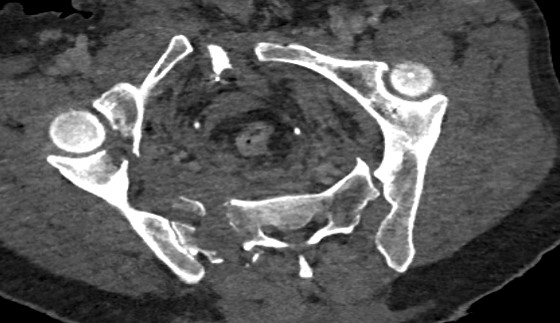

Et, paradoxalement, l'IA peut tout à fait spotter des petites anomalies mais rater des choses ENORMES au calme. Exemple ici avec un énorme fracas du bassin où l’algorithme répondait qu’il n’y avait pas de fracture. Bref: les humains et l’IA ne font pas les mêmes erreurs. (21/32)